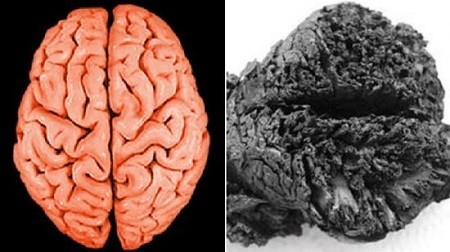

Қазіргі адам миымен салыстырма суреті

Ми арқылы жасалған Қола дәуір адамының жорамал суреті